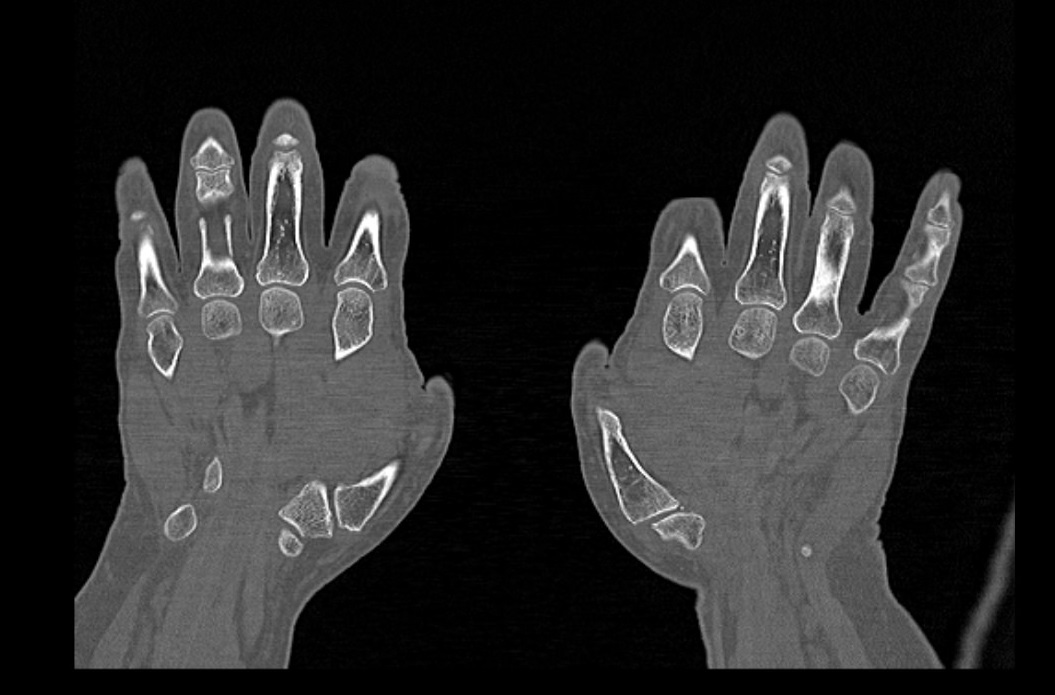

Мультиспиральная компьютерная томография является наиболее точным и информативным методом диагностики травматических повреждений и различных заболеваний костей и суставов пальцев рук. КТ относится к лучевым методам обследования, то есть основан на применении рентгеновского излучения. Быстрота выполнения, неинвазивность (не нужно вмешательство в организм), доступная стоимость делают это исследование незаменимым в травматологии и ортопедии. С помощью КТ проводится диагностика вывихов, ушибов, переломов костей пальцев руки.

При помощи проникающей способности рентгеновских лучей томограф производит послойное сканирование исследуемой области. В результате получаются детальные снимки, а после цифровой обработки данных – подробные трехмерные изображения кисти и пальцев руки.

В наших медицинских центрах КТ пальцев рук выполняется на новейших мультиспиральных компьютерных томографах экспертного уровня TOSHIBA AQUILION. Современное оснащение аппаратов позволяет получать детальные изображения высокого уровня четкости и контрастности, что обеспечивает точность и достоверность диагностики. При этом за счет скоростного мультисрезового сканирования пациент получает уменьшенную дозу рентгеновского облучения.